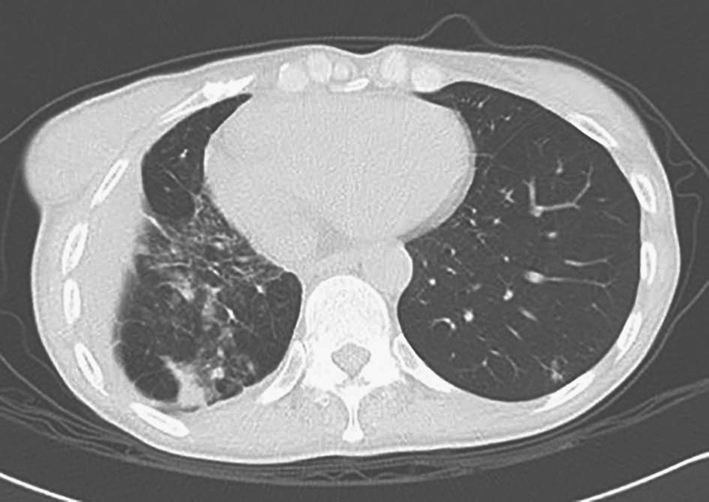

四、影像学检查

胸部CT提示“右中肺机化性肺炎较前加重”(图3),肌电图大致正常。

图3 2011年3月8日CT示右中肺机化性肺炎较前加重

更昔洛韦抗病毒抢先治疗[具体方案为更昔洛韦静脉滴注300mg/次,q12h(每12小时1次),2周后减至300mg/d,再用2周后改为口服更昔洛韦500mg/次,3次/d,2个月],甲泼尼龙1g/d × 3d冲击联合环磷酰胺400mg,q2w(每2周1次),治疗后症状迅速缓解,但缓解1周后症状反复,反复查巨细胞病毒抗原均阴性,痰培养提示烟曲霉阳性,复查胸部CT提示“右中肺机化性肺炎较前吸收、右下肺支气管胸膜瘘和左肺真菌感染”,考虑为治疗过程中并发真菌感染,细菌感染不能除外,遂将甲泼尼龙减量为60mg/d静脉滴注,停用环磷酰胺,加用伊曲康唑200mg/d、哌拉西林舒巴坦5g,q12h静脉滴注,充分抗感染治疗,此后复查CT提示“机化性肺炎逐渐吸收,支气管胸膜瘘及肺部感染范围亦逐渐减小”(图4),体温正常,症状好转出院。

图4 2011年4月胸部CT示机化性肺炎明显好转